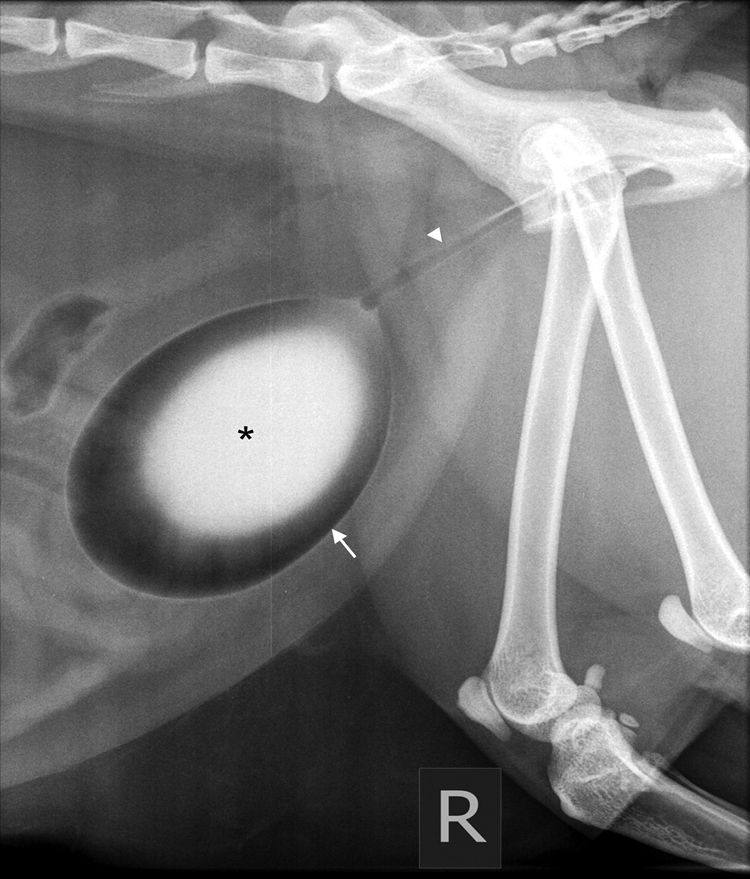

Describe this retrograde urethrography radiograph (dog)?

Membranous urethra is wider (normal)

Fabella of femur can look like caliculi so pull legs forward

No contrast leakage